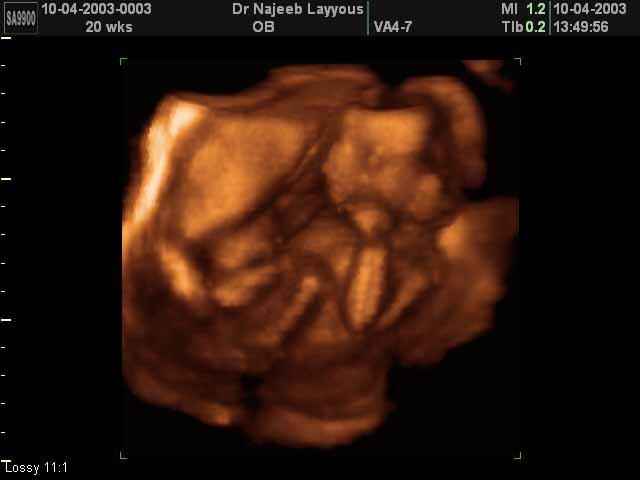

3D second trimestre échographie Photos de numérisation - deuxième partie de la grossesse | Dr N Layyous

3D second trimestre échographie Photos de numérisation - deuxième partie de la grossesse